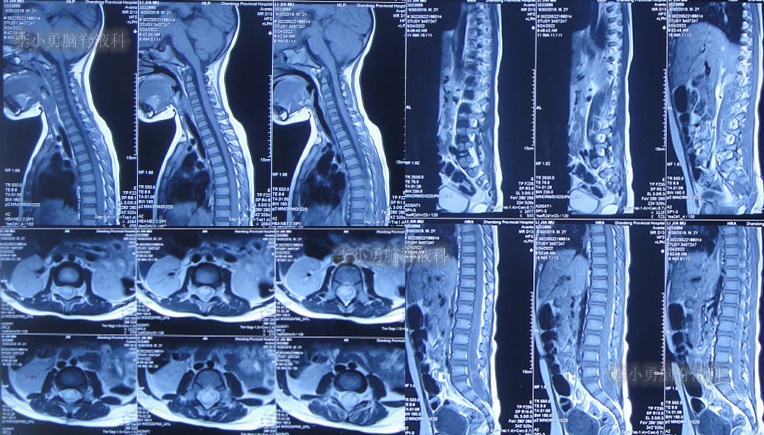

在第2家医院治疗13天即2022年5月24日,患儿仍间断高热,在医生建议下当天转至上级的第3家医院山东省某省级三甲医院,查脊髓核磁(图-2)后行腰椎穿刺有脓液吸出,给予腰大池置管术,但未见脑脊液流出,给予消炎、营养脑神经治疗。

图-2:2022年5月24日脊髓核磁